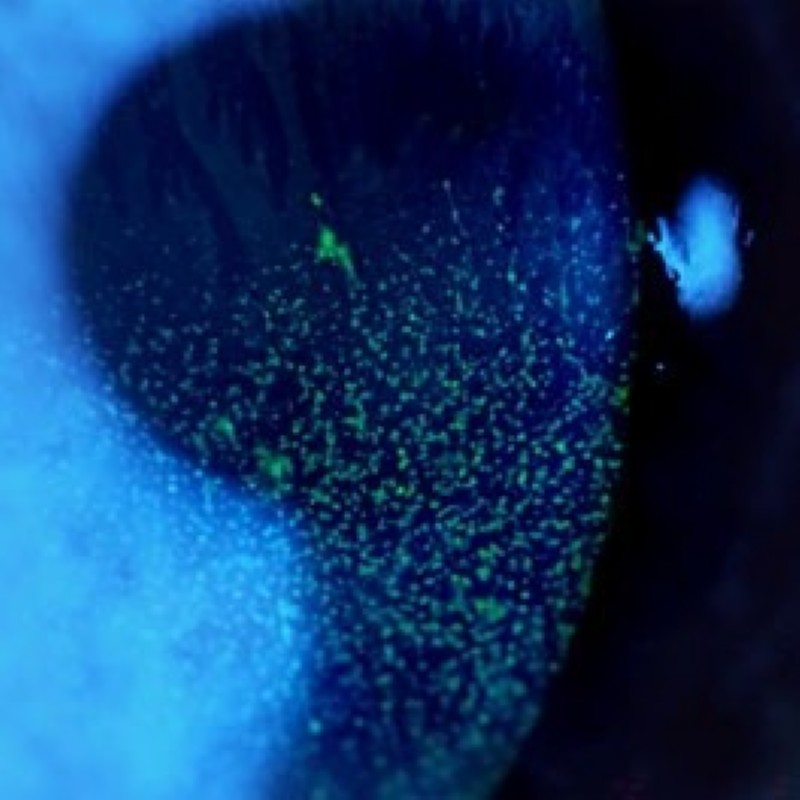

Hornhautentzündung (Keratitis)

Leichte Form bis zum Geschwür (Ulcus) möglich.

Symptome: Rötung, Fremdkörpergefühl, Brennen, Jucken, Sekretion, Augenrinnen, Verschwommensehen.

Ursachen: Bakterien, Viren (z. B. Herpes), Pilze, häufig kontaktlinsenbedingt (Verunreinigung der Kontaktlinsen und/ oder Reinigungslösung und Kontaktlinsenbehälter).

Therapie: Augentropfen, Augensalbe - je nach Schweregrad auch systemische Therapie nötig, in bestimmten Fällen allergische, virale, bakteriologische und zytologische Abklärung.